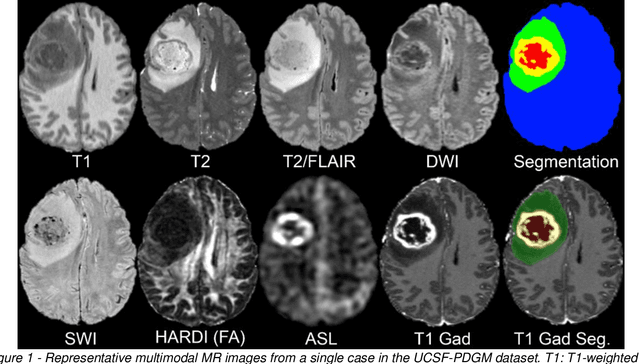

Abstract:Here we present the University of California San Francisco Preoperative Diffuse Glioma MRI (UCSF-PDGM) dataset. The UCSF-PDGM dataset includes 500 subjects with histopathologically-proven diffuse gliomas who were imaged with a standardized 3 Tesla preoperative brain tumor MRI protocol featuring predominantly 3D imaging, as well as advanced diffusion and perfusion imaging techniques. The dataset also includes isocitrate dehydrogenase (IDH) mutation status for all cases and O6-methylguanine-DNA methyltransferase (MGMT) promotor methylation status for World Health Organization (WHO) grade III and IV gliomas. The UCSF-PDGM has been made publicly available in the hopes that researchers around the world will use these data to continue to push the boundaries of AI applications for diffuse gliomas.